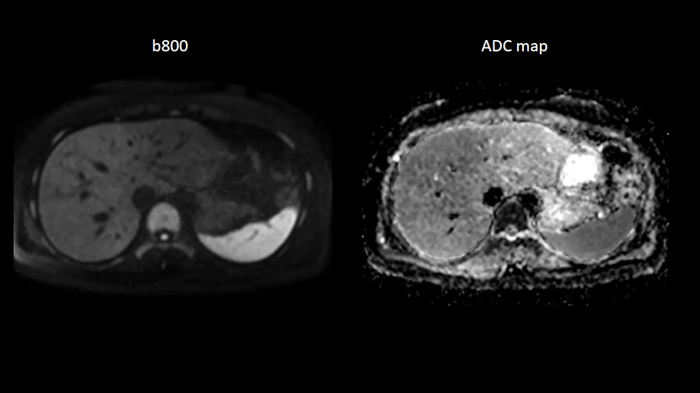

Abdomen

Body diffusion imaging

For all-inclusive abdominal MR capabilities, outstanding quality diffusion imaging.

MAC-ID: 7aaaa0165. Image Credit: Siemens Healthineers

T2 BLADE

T2 motion insensitive abdominal imaging with BLADE results in outstanding outcomes, regardless of the orientation or if fat saturation is needed.

MAC-ID: 7aaaa0165. Image Credit: Siemens Healthineers